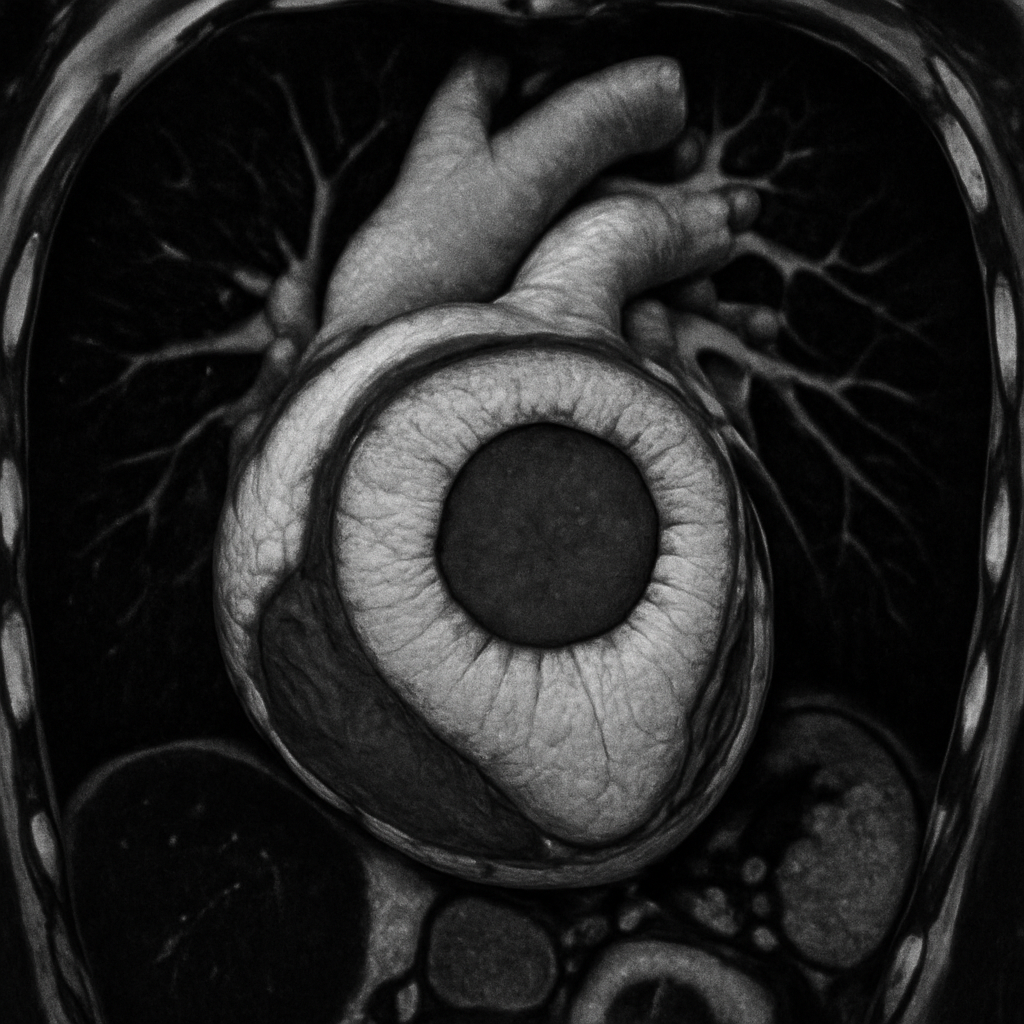

AI-generated comprehensive cardiac phantom with all four chambers, valves, coronary arteries, great vessels, pericardium, and surrounding structures for multi-modality cardiac imaging training

Modalities: CT MRI ULTRASOUND PET SPECT DIGITAL RADIOGRAPHY